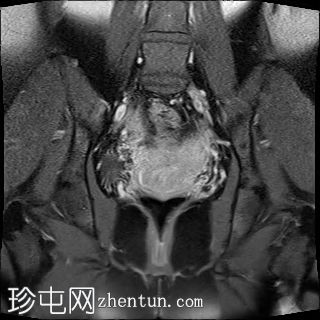

冠状位

T2加权像

双侧卵巢位置接近(卵巢相吻),左侧卵巢内可见一边界清晰的囊性病变,大小约3.1 × 2.7 × 2.9 cm,T1加权像呈高信号,T2加权像可见暗点征及内部暗点征。以上MRI特征符合卵巢子宫内膜异位囊肿的诊断。

右侧卵巢可见一囊肿,大小约为 2.8 × 2.0 × 2.2 cm,T1 加权像呈高信号,囊内可见液-液平面,提示囊内含有不同时期的出血性物质。由于对侧卵巢存在典型的子宫内膜异位囊肿,且该囊肿无强化,影像学表现强烈提示为另一子宫内膜异位囊肿。

双侧卵巢均可见多个小卵泡。

子宫大小、轮廓及信号强度均正常,子宫内膜分区结构完整。未见局灶性肌层病变,子宫内膜厚度在正常范围内。